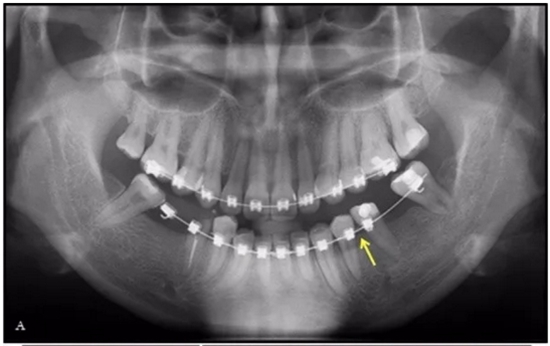

完全固定的Damon Q設(shè)備(加利福尼亞州Glendora的Ormco)與制造商指定的弓絲和附件一起使用。下頜弓,一開(kāi)始放入0.014英寸的鎳鈦弓絲,5個(gè)月后放入0.014×0.025英寸的鎳鈦弓絲。舌側(cè)扣和鏈圈放置在下頜尖牙和第二前磨牙上以控制扭轉(zhuǎn)。在治療的第7個(gè)月,將下頜弓絲換成0.017× 0.025英寸的β鈦絲。另一個(gè)舌側(cè)扣和鏈圈放置在下頜左側(cè)第三磨牙上以提供近中牽引力(圖9)。在16個(gè)月的治療結(jié)束時(shí),所有的扭轉(zhuǎn)都得到了矯正,缺牙間隙縮小到8 mm(圖8),但由于頰側(cè)骨板的嚴(yán)重吸收,牙槽嵴的寬度仍然很窄(約3 mm)(圖9)。通過(guò)正畸移動(dòng)下頜左側(cè)第二前磨牙,在前磨牙之間產(chǎn)生一個(gè)種植部位。在第一和第二前磨牙之間的弓絲上放置一個(gè)推簧,并將舌側(cè)扣和鏈圈放置在第一前磨牙和第三磨牙之間(圖9),在頰側(cè)和舌側(cè)施加力。施力均為輕力,每個(gè)表面上約2盎司(28.3 cN)以控制牙根側(cè)面的吸收。

圖10.經(jīng)過(guò)7個(gè)月后,以每月1毫米的速度牽引下頜左側(cè)第二前磨牙,正畸產(chǎn)生的種植部位長(zhǎng)約7毫米。通過(guò)使用固定矯治器保持間隙6個(gè)月。根尖X線(xiàn)片顯示第二前磨僅有少量牙根遠(yuǎn)中面吸收。

經(jīng)過(guò)32個(gè)月的活動(dòng)治療后,上下牙弓排齊良好,下頜第一磨牙區(qū)的雙側(cè)牙間隙可用于種植(圖12,A和13,A)。